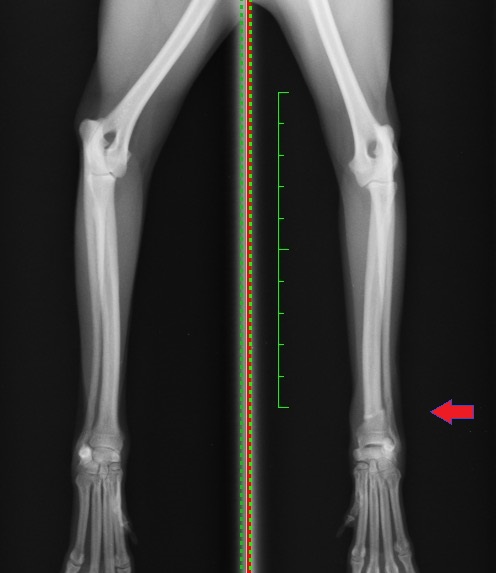

2枚目プレート抜去後

次のX線写真は2枚目のプレート抜去後になります。

橈骨・尺骨共にしっかりと骨折部位が癒合しているのが分かります。 このように段階的にプレートを抜去し、骨への負荷を高めることで、プレート抜去後に多い再骨折を予防することができます。